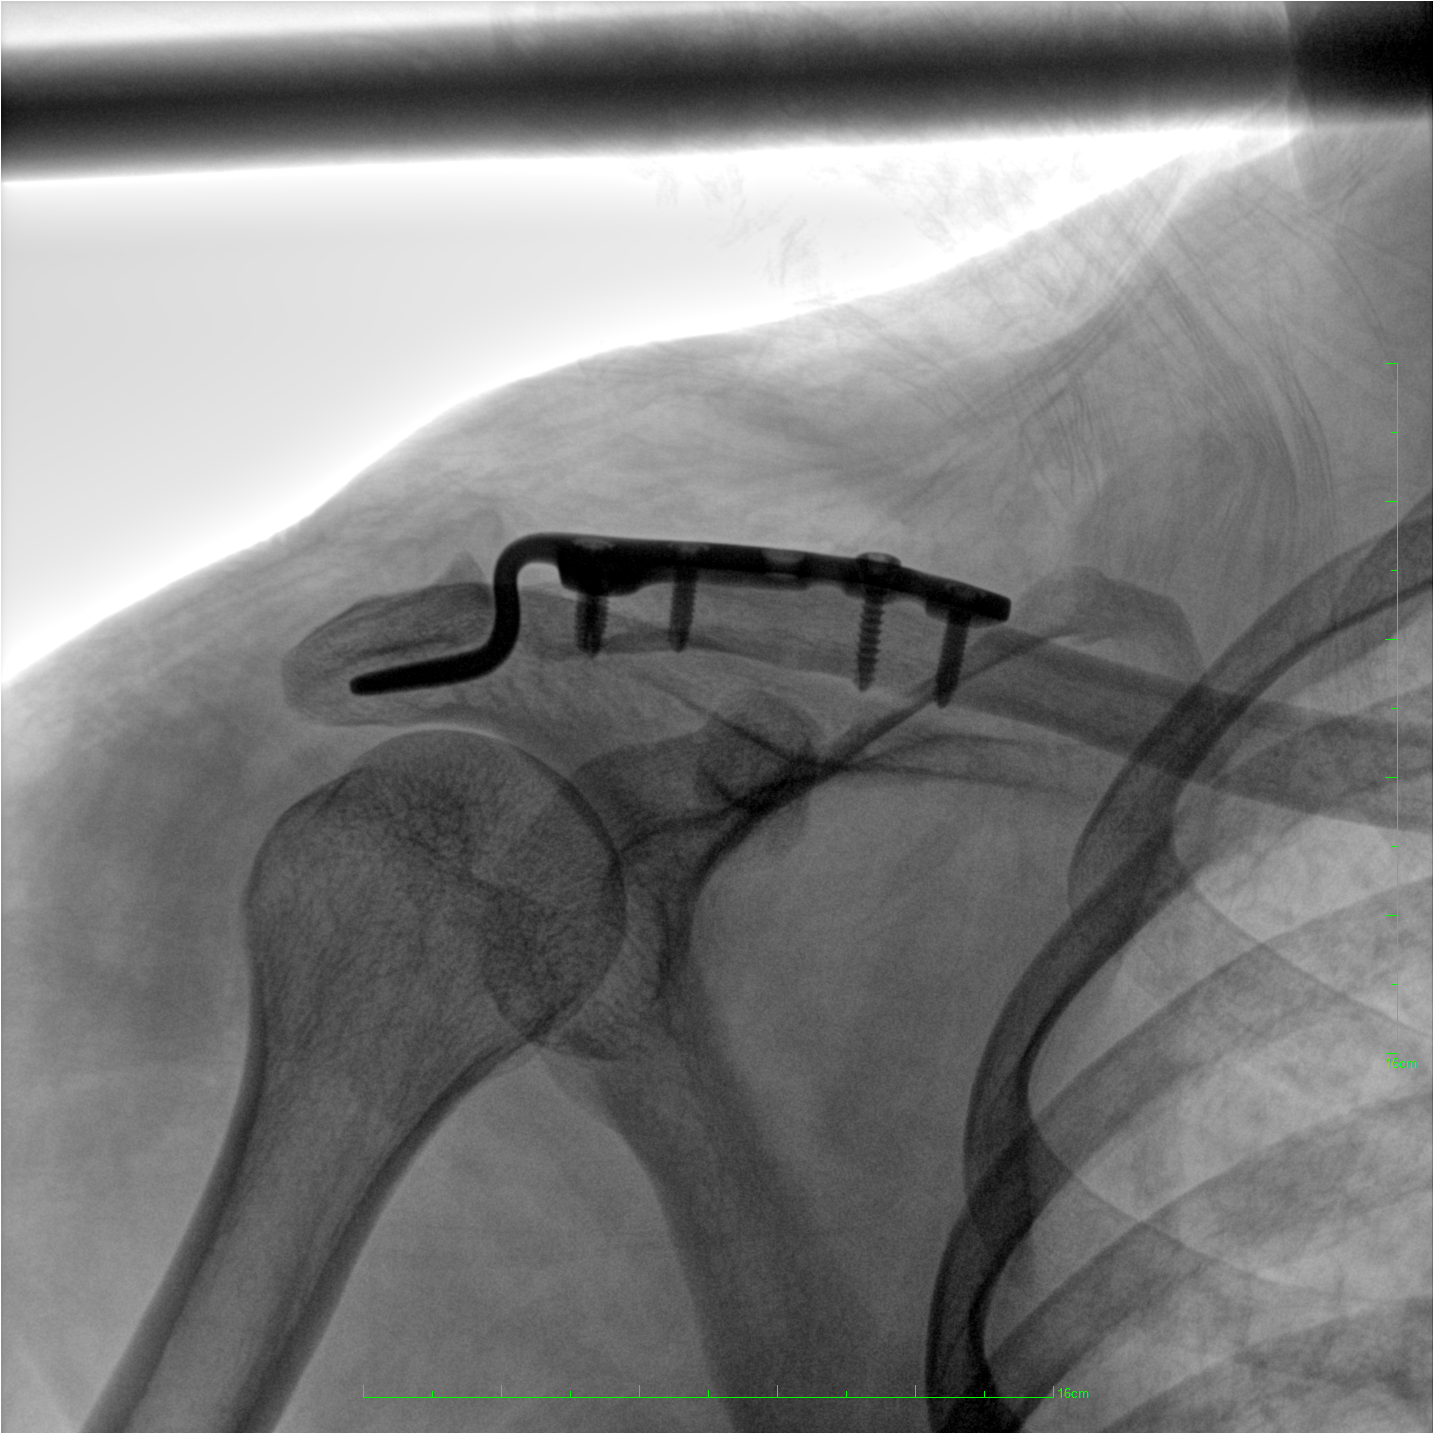

術(shù)中三維成像和橫斷面圖像提供多角度的手術(shù)診斷信息,輔助醫(yī)生進(jìn)行術(shù)中評(píng)估判斷,諸如骨折復(fù)位情況和內(nèi)植入螺釘?shù)某叽绾臀恢茫o助手術(shù)更好地完成。

提供更大的術(shù)中三維成像視野,采集更多圖像信息,可一次拍全全段頸椎、全段腰椎、七節(jié)胸椎、雙側(cè)骶髂關(guān)節(jié)、股骨頭及單側(cè)盆骨。